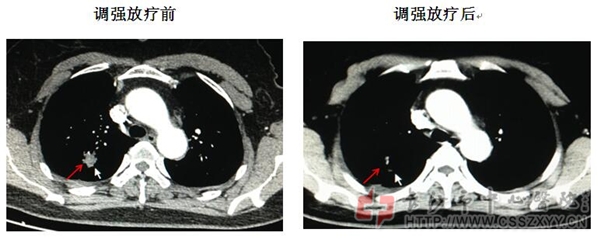

右肺腺癌调强适形放疗效果